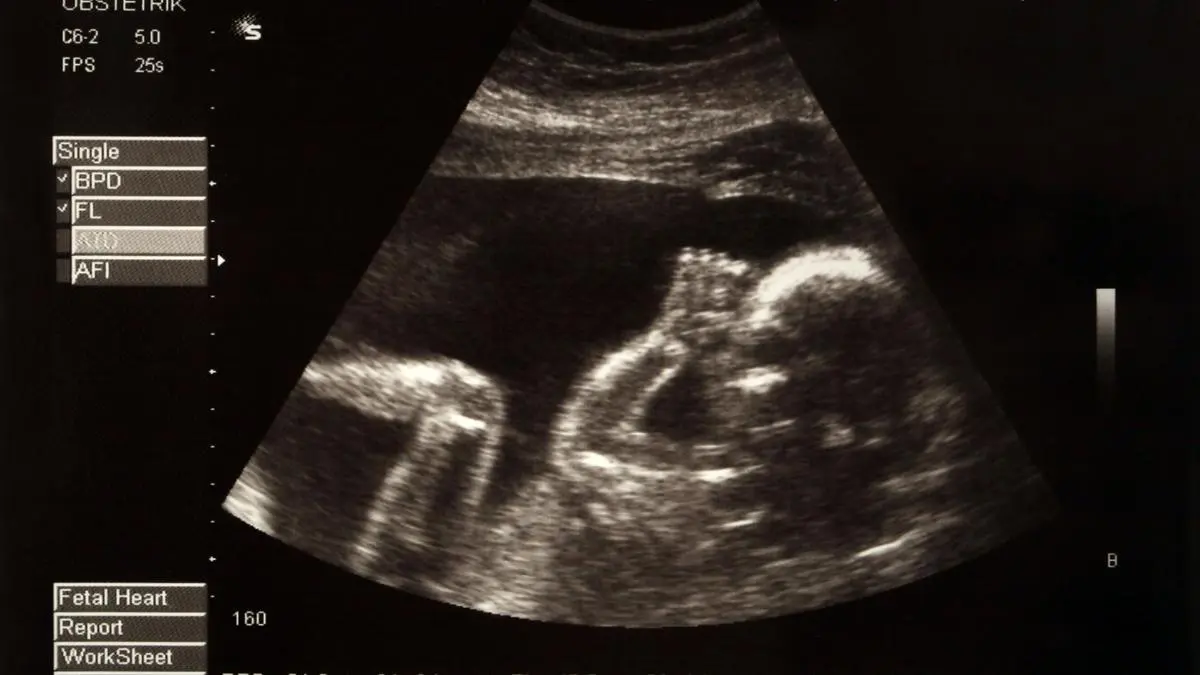

Covid-19-Impfung ist nicht für Anstieg von Totgeburten verantwortlich

Nicht die Verabreichung des Covid-19-Impfstoffes hat zu einem Anstieg der Totgeburten in Singapur geführt, sondern die veränderte Zählweise der Behörden.

Covid-19-Impfung schützt Schwangere und deren Babys